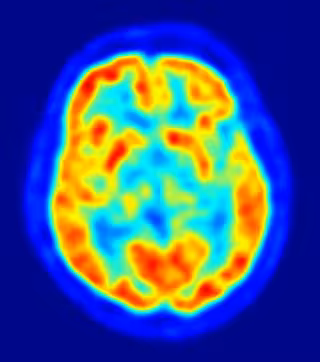

cerebro, alzheimer

Científicos del Centro de Investigación en Imagen Clínica de la Universidad de Washington, en Estados Unidos, han mostrado en el 57 Encuentro Anual SNM, que se celebra en Salt Lake City hasta este miércoles, 9 de junio, sus progresos en el uso de imágenes PET para seguir las etapas tempranas de la enfermedad de Alzheimer. Este hallazgo podría llevar al descubrimiento de medidas preventivas que beneficiarán a millones de pacientes que sufren este desorden neurodegenerativo crónico.

En uno de los pocos estudios longitudinales realizados a gran escala sobre este fenómeno, los científicos usaron una tomografía por emisión de positrones (PET, por sus siglas en inglés) para documentar los cambios que se producen durante la acumulación de beta-amiloides, que forman placas en los tejidos neuronales de los pacientes a los que se les diagnostica Alzheimer.

El PET y otras técnicas de imagen molecular ayudan a los investigadores a entender el inicio de la patología para determinar el mejor tratamiento para cada paciente, incluso antes de que aparezcan síntomas como la pérdida de memoria, las dificultades para pensar o la habilidad para realizar tareas simples. Según Mintun, "con este tipo de investigaciones, los médicos podrán recomendar el tratamiento antes de que se den daños irreversibles en el cerebro del afectado".

Un total de 129 personas, con edades entre los 45 y los 86 años y sin síntomas de padecer un desorden cognitivo, participaron en este estudio. Se sometieron a escáneres con PET en un periodo de cinco años, usando el Pittsburgh Compound-B (11C-PIB), un agente de imagen PET que muestra los beta-amiloides en el cerebro.